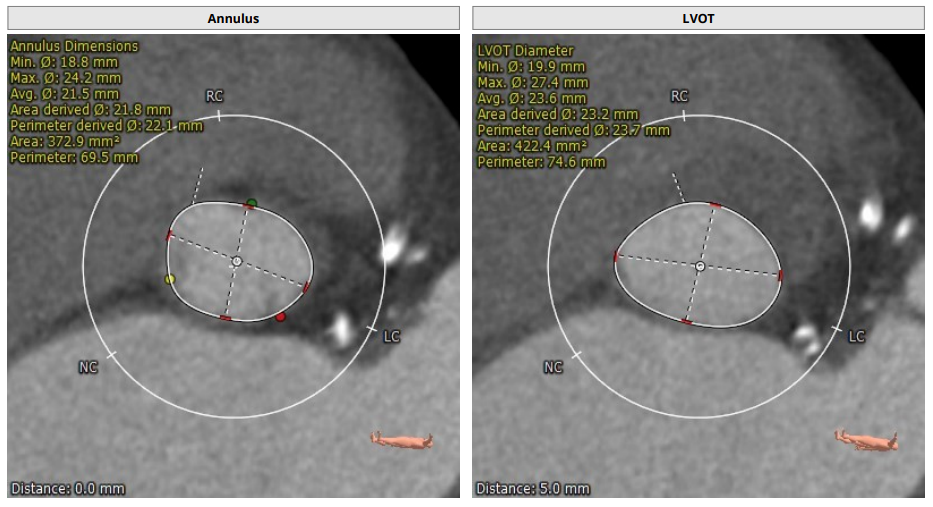

主动脉根部解剖CT影像

瓣环平均直径:22.1 mm,左室流出道平均直径:23.7mm。

左冠高度:9.6 mm,右冠高度:16.1 mm。

钙化积分:221.4mm³。